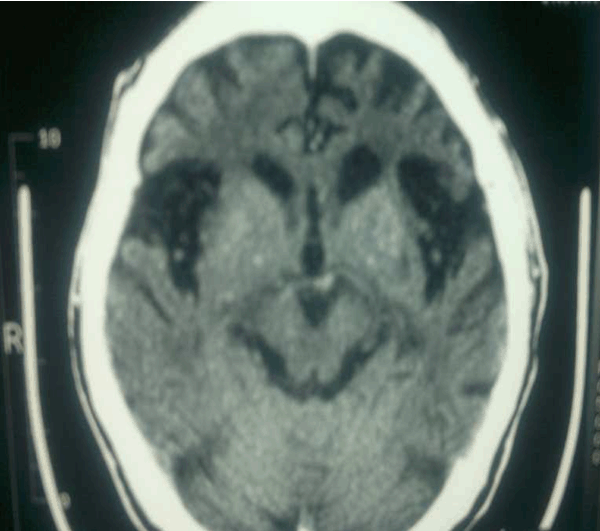

Patient's full blood count, renal functions, thyroid functions, liver functions and routine urine examinations were normal. He tested negative for HIV, Hepatitis B, Hepatitis C, venereal disease research laboratory test (VDRL), and treponema palladium hemagglutination test (TPHA). His serum electrolytes were normal. Based on the history and clinical presentation, a diagnosis of dementia with Herpes simplex of left thigh was considered. Computed tomography scan of the brain showed atrophy of frontal and temporal areas of the brain. (Figure 1) (Figure 2) (Figure 3) (Figure 4)

Figure 1: Bifrontotemporal atrophy and prominent sylvian fissures. Frontal horns of ventricles are just visible.

Macroscopic examination of the brain of a patient with FTLD typically shows symmetrical focal atrophy of the frontal lobes, temporal lobes. Microscopic examination of the cerebral cortex in most forms of FTLD, shows microvacuolation and neuronal loss. On staining for deposits in neurons, abnormal tau protein aggregates (46%) and ubiquitin-positive inclusions (29%) were found.[6] Our patient had frontal and temporal lobe atrophy on CT scan. The exact etiology and pathophysiology of frontotemporal dementia is incompletely understood but recent studies suggest that genetics plays an important role in disease causation. [7] This is supported by the fact that about 50% of patients with frontotemporal dementia (FTD) report a positive family history. [7]